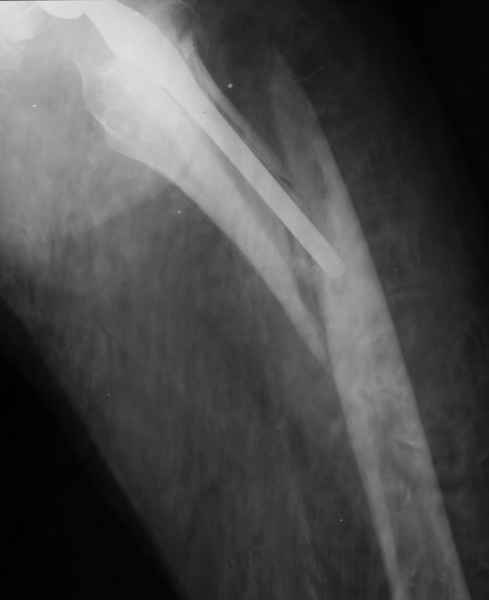

Закрытый остеосинтез-удлинение ножки (подход далеко не общепринятый, и пока даже не общеизвестный)- наименее инвазивный вариант, который обеспечивает немедленное восстановление опороспособности. Конечно, хотелось бы, чтобы эта операция решила проблему окончательно, т.е. в

ближайшие годы других больших операций не потребовалось бы.

ножка просела немного (вопрос, много - это сколько?)перечисленные проблемы - не самое важное сейчас, на них можно закрыть глаза. Ножка явно нестабильна, проксимальный отломок с б/вертелом к гвоздю не прицепить, срастется ли он с ножкой

1.Остеосинтез на ножке. Мне кажется, что применительно к этому случаю малоперспективный вариант. Синтез хорош, когда можно его выполнить в малоинвазивном исполнении и достигнуть стабильности. Действительно, если ножка б/цементной фиксации после этого не будет иметь фиксации, то ревизия не будет иметь проблем. В представленном случае стабильность синтеза сомнительная, а проведение доп.иммобилизации приведет к контрактуре суставов.